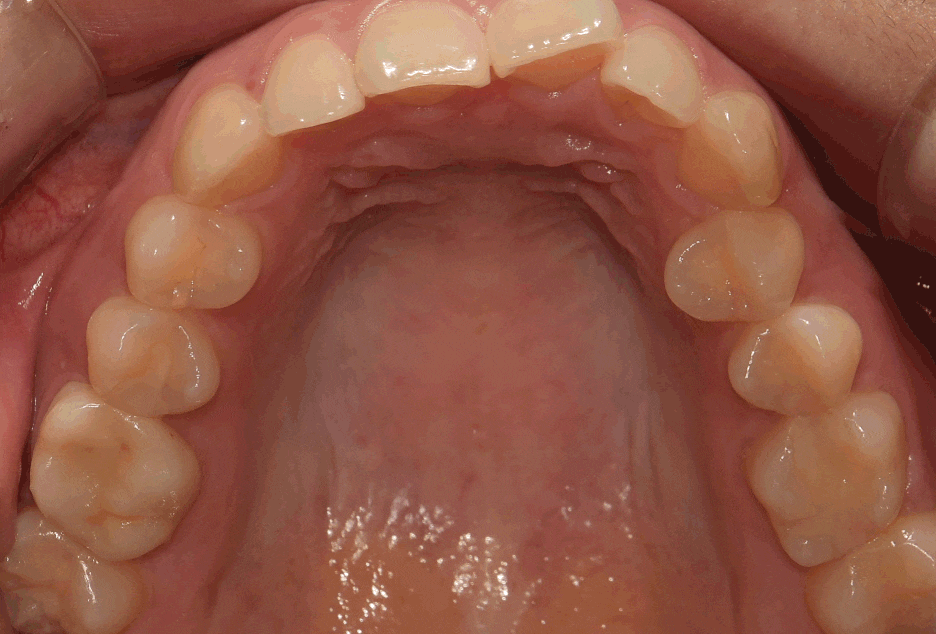

구강 내 사진을 먼저 보여드리면, 윗니가

아랫니를 깊게 물고 있어서 아랫니가 거의

눈에 띄지 않는 것을 보실 수 있습니다.

딱, 전형적 과개교합 의 양상을 보여주고 있습니다.

그러면서 치아의 중심선이 맞지 않으면서

악궁의 크기 또한 비대칭인것을 볼 수 있네요.